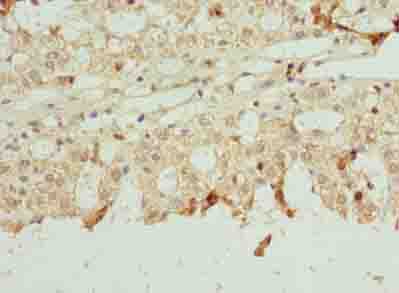

ApplicationELISA, WB, IHC; Recommended dilution: WB:1:1000-1:5000, IHC:1:20-1:200